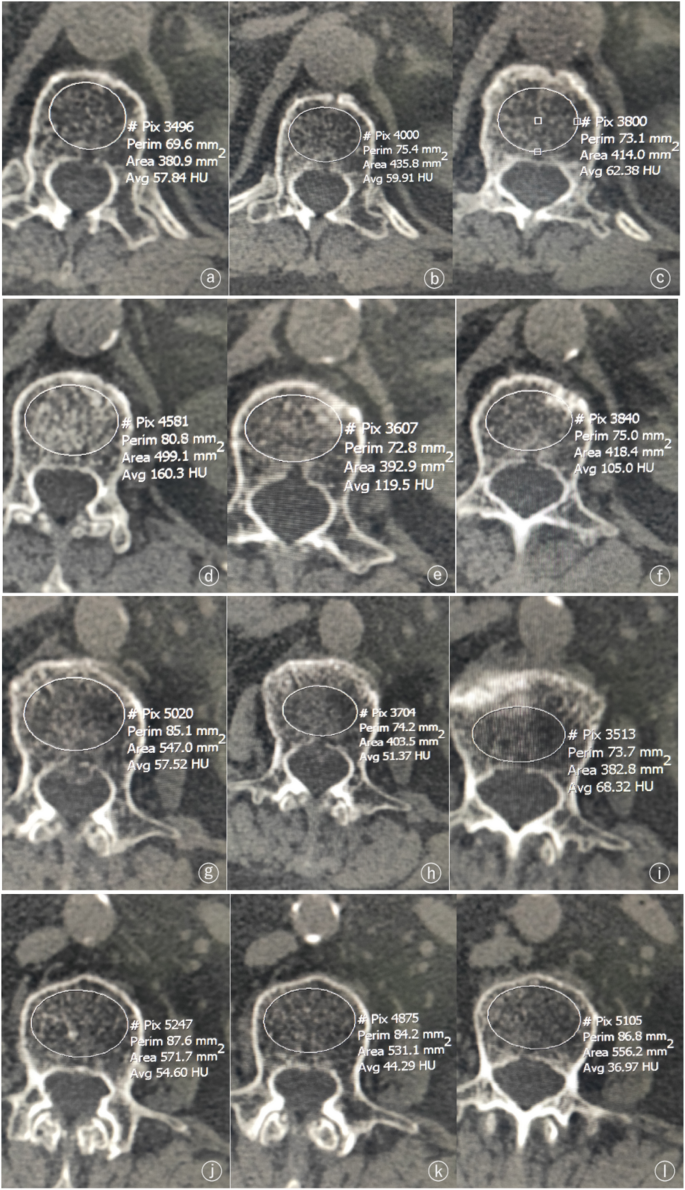

Feasibility study in quantitative identification of fresh and old  osteoporotic vertebral compression fracture by vertebral CT value and CT  value difference | BMC Musculoskeletal Disorders